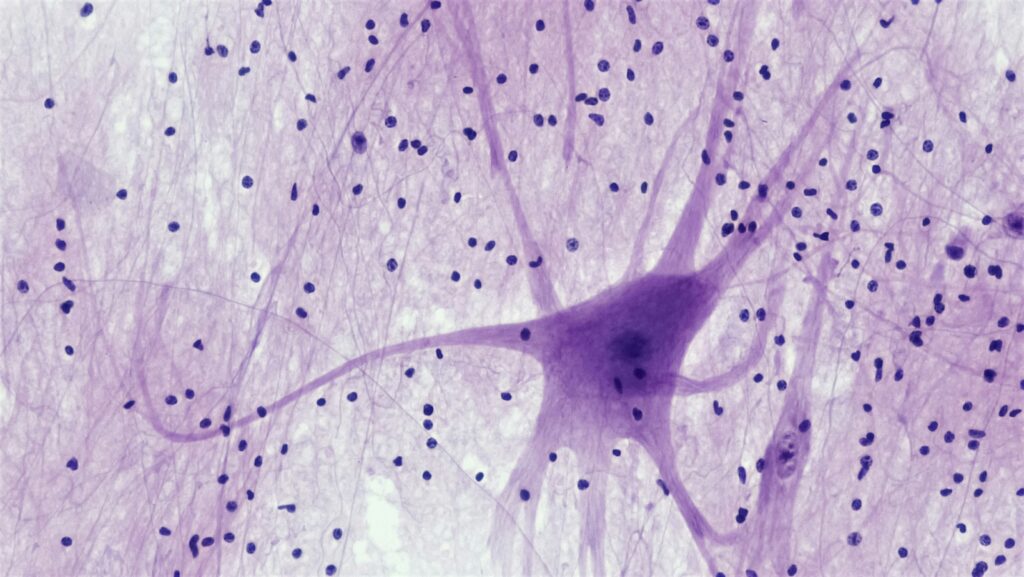

A nerve conduction study is one of the most common diagnostic tests used to evaluate how well your peripheral nervous system is sending electrical signals along a nerve pathway. Because nerves control sensation and movement, changes in signal speed or strength can help your clinician understand whether symptoms are more consistent with peripheral neuropathy, peripheral nerve damage, or another category of nerve disorders.

A nerve conduction study measures how quickly and how strongly a nerve carries electrical impulses. During the test, the clinician uses electrical stimulation to briefly stimulate a nerve and then records the response downstream. This helps evaluate how signals move through the peripheral nervous system.

Your spinal cord acts like a central highway for signals traveling between the body and the brain, but many symptoms start “downstream” in the peripheral nervous system. When peripheral nerves aren’t carrying messages properly, you may notice changes in sensation, reflexes, strength, or coordination—even when the brain itself is not the primary problem.